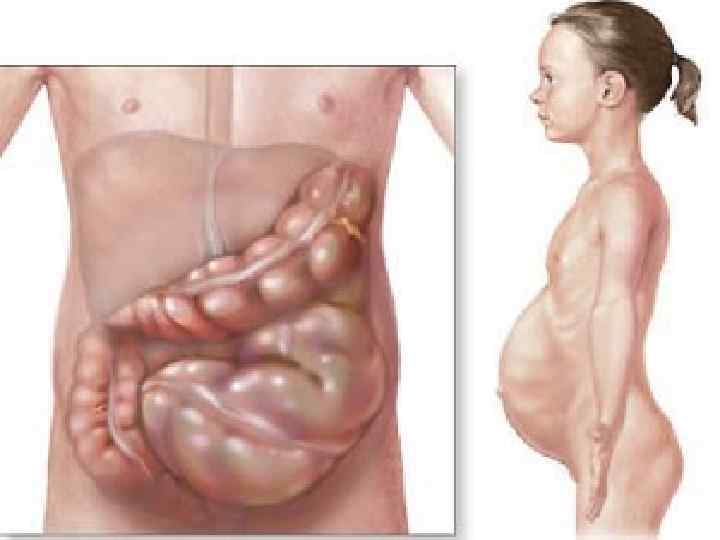

Механическая и динамическая непроходимость кишечника Анамнез Ведущими симптомами острой кишечной непроходимости являются боли в животе, его вздутие, рвота, задержка стула и газов. Они имеют различную степень выраженности в зависимости от вида непроходимости, уровня и длительности заболевания. Боли обычно возникают внезапно, вне зависимости от приема пищи, в любое время суток, без каких либо предвестников. Им свойственен схваткообразный характер, связанный с периодами гиперперистальтики кишечника, без четкой локализации в каком либо отделе брюшной полости. При обтурационной кишечной непроходимости вне схваткообразного приступа они обычно полностью исчезают. Странгуляционной непроходимости свойственны постоянные резкие боли, периодически усиливающиеся. При прогрессировании заболевания острые боли, как правило, стихают на 2 3 и сутки, когда перистальтическая активность кишечника прекращается, что служит плохим прогностическим признаком.

Клиническая картина Основные симптомы: Боль без четкой локализации, схваткообразная или постоянная с разной степенью интенсивности. симптом Тэвенара – боль при пальпации на 2 поперечных пальца ниже пупка(проекция корня брыжейки тонкой кишки). При странгуляционной непроходимости. вздутие живота – может быть симметричным и ассиметричным(странгуляционная). Характерно для высокой непроходимости. видимая перистальтика – характерна для механической непроходимости. Рвота – многократная, ненадолго приносящая облегчение, переходящая постепенно в каловую рвоту. симптом Валя – высокий тимпанит над проекцией толстой кишки – характерно для ранней механической непроходимости. симптом Шимана – западение живота в левой подвздошной области, в то время как в правом подреберье вздутие толстого кишечника, при завороте сигмовидной кишки. симптом Склярова – шум плеска при сукуссии. симптом Спасокукоцкого Вильмса – шум падающей капли, растянутые петли кишечника. Аускультация живота, по образному выражению наших хирургических учителей, необходима для того, чтобы «услышать шум начала и тишину конца» (Г. Мондор). «гробовая тишина» отсутствие перистальтики. пальцевое ректальное исследование – «каловый завал» , вздутие ампулы. интоксикационный синдром – температура, тахикардия, головная боль и слабость – признак калового застоя.